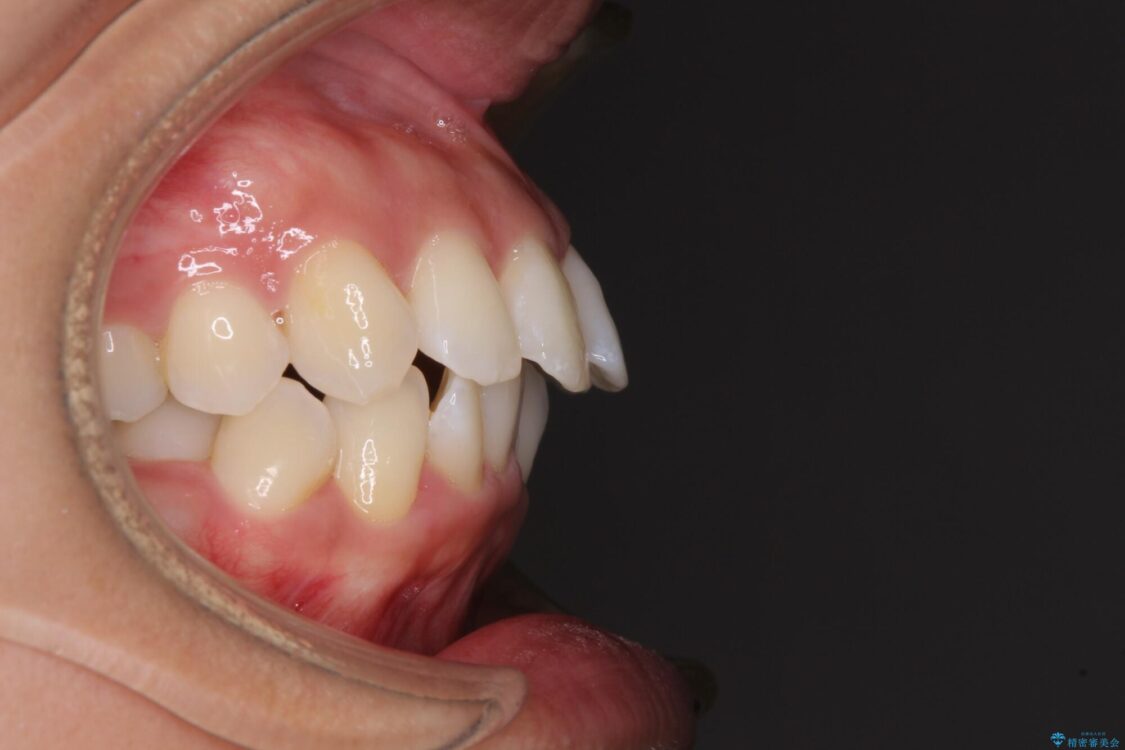

治療後について

抜歯スペースに前歯を移動させることで歯の突出感が改善され、非常に唇が閉じやすい仕上がりとなりました。

治療後